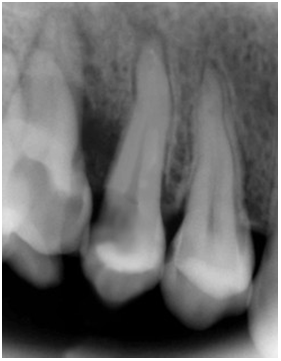

A 22-year old female patient presented in our private dental practice set up with complaint of pain, food stagnation, foul smell and loosening of couple of teeth in upper jaw. Intraoral examination revealed vertical bone loss around distal surface of upper right second premolar and mesial surface of first molar (Figure 1). The pocket depth was measured to be more than 15mm (Figure 2). The severely affected premolar and molar, on pulp testing showed pulpal involvement leading to diagnosis of endo-periodontal lesion.